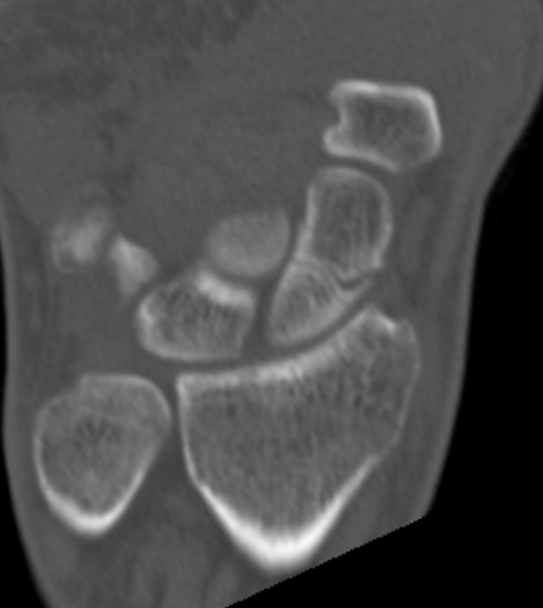

CT

Indication

- diagnose nonuion

- identify humpback deformity

- plan size and shape of bone graft

Failure of fracture to unite at 3 months on CT scan

Nonunion with flexion deformity